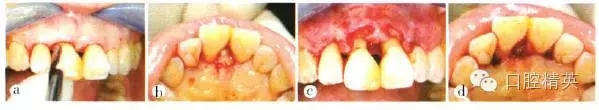

患者全身狀況良好,無過敏史及長期服用藥物史,否認(rèn)吸煙史??谇粰z查:口腔衛(wèi)生尚好,菌斑、軟垢少,牙石+~++;個別牙齦輕度紅腫,出血指數(shù)(bleeding index,BI)為1~3,654 456牙齦退縮明顯;全口探診深度(probe depth,PD)3~5 mm,附著喪失,根分叉病變(furcation involvement,F(xiàn)I)個別1~2度,無松動;7缺失,1先天缺失,雙側(cè)第一磨牙近中關(guān)系。高位笑線,前牙I度深覆蓋,211牙冠呈尖圓形,牙齦退縮約1.3 mm,齦乳頭缺失,屬Miller III類.鄰面根頸部可見“黑三角”(圖1)。

a上前牙區(qū)正面觀;b上前牙區(qū)牙合面觀;c上前牙區(qū)腭側(cè)觀;d患者微笑像,可見上前牙區(qū)存在“黑三角”;e上前牙區(qū)側(cè)面觀

圖1初診時上前牙區(qū)口內(nèi)像及微笑像